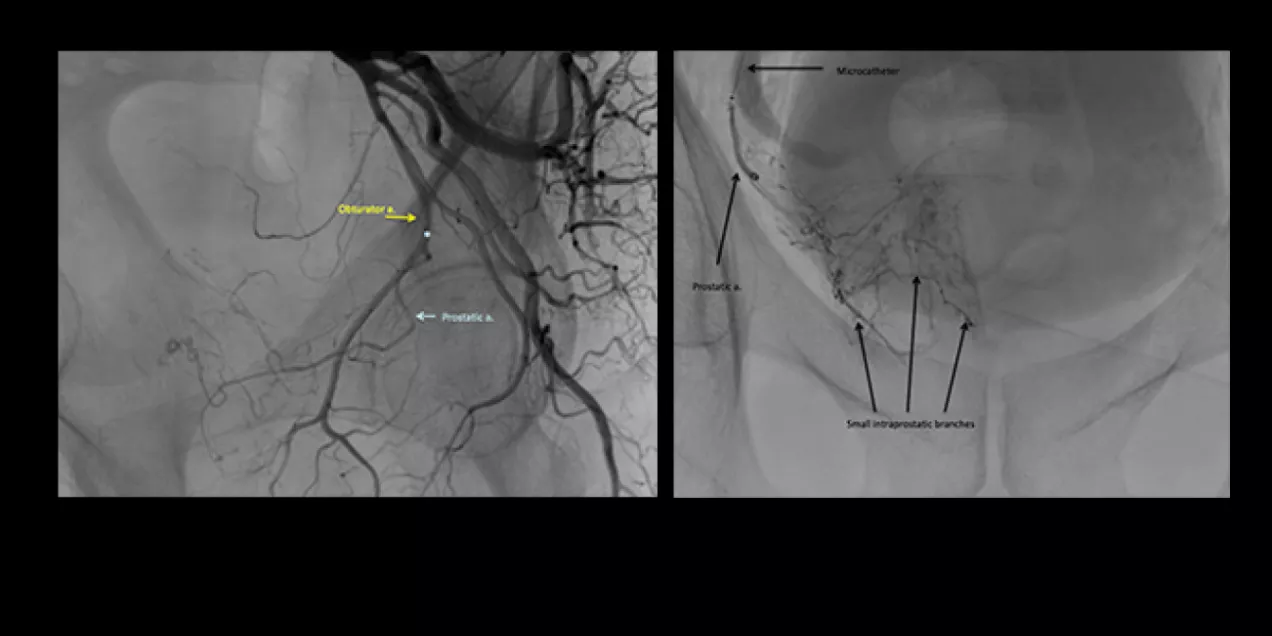

Figure 2

A tiny catheter is then advanced into the vessel supplying blood to the prostate. Advanced imaging techniques are then used to confirm appropriate positioning of the microcatheter. Once appropriate positioning is confirmed, small particles (microspheres) are injected through the microcatheter. The result is cessation of blood flow in the prostatic artery. As most patients have two prostatic arteries (left and right), the process is repeated on the opposite side before the catheter is removed. See Figure 2 to the left.